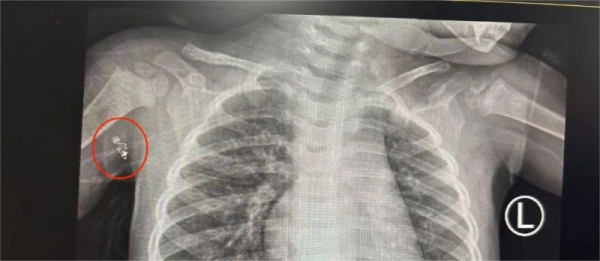

入院后完善相关检查,彩超提示:右腋窝皮下局部可见一液性暗区,约11mm*10mm*4mm,深方可见一肿大淋巴结约12mm*6mm,结合CT等检查基本可明确躯干浅表异物是水银在皮下残留,有手术指征,应尽早行手术治疗。

日间手术中心副主任徐维立即为瑾瑾进行手术治疗,术中见水银残端位于皮下软组织深部,紧贴腋下大血管及腋神经,周围可见淋巴结明显肿大,在手术团队的精湛操作下,顺利取出异物,术后拍片检查,确认异物已完全清除。